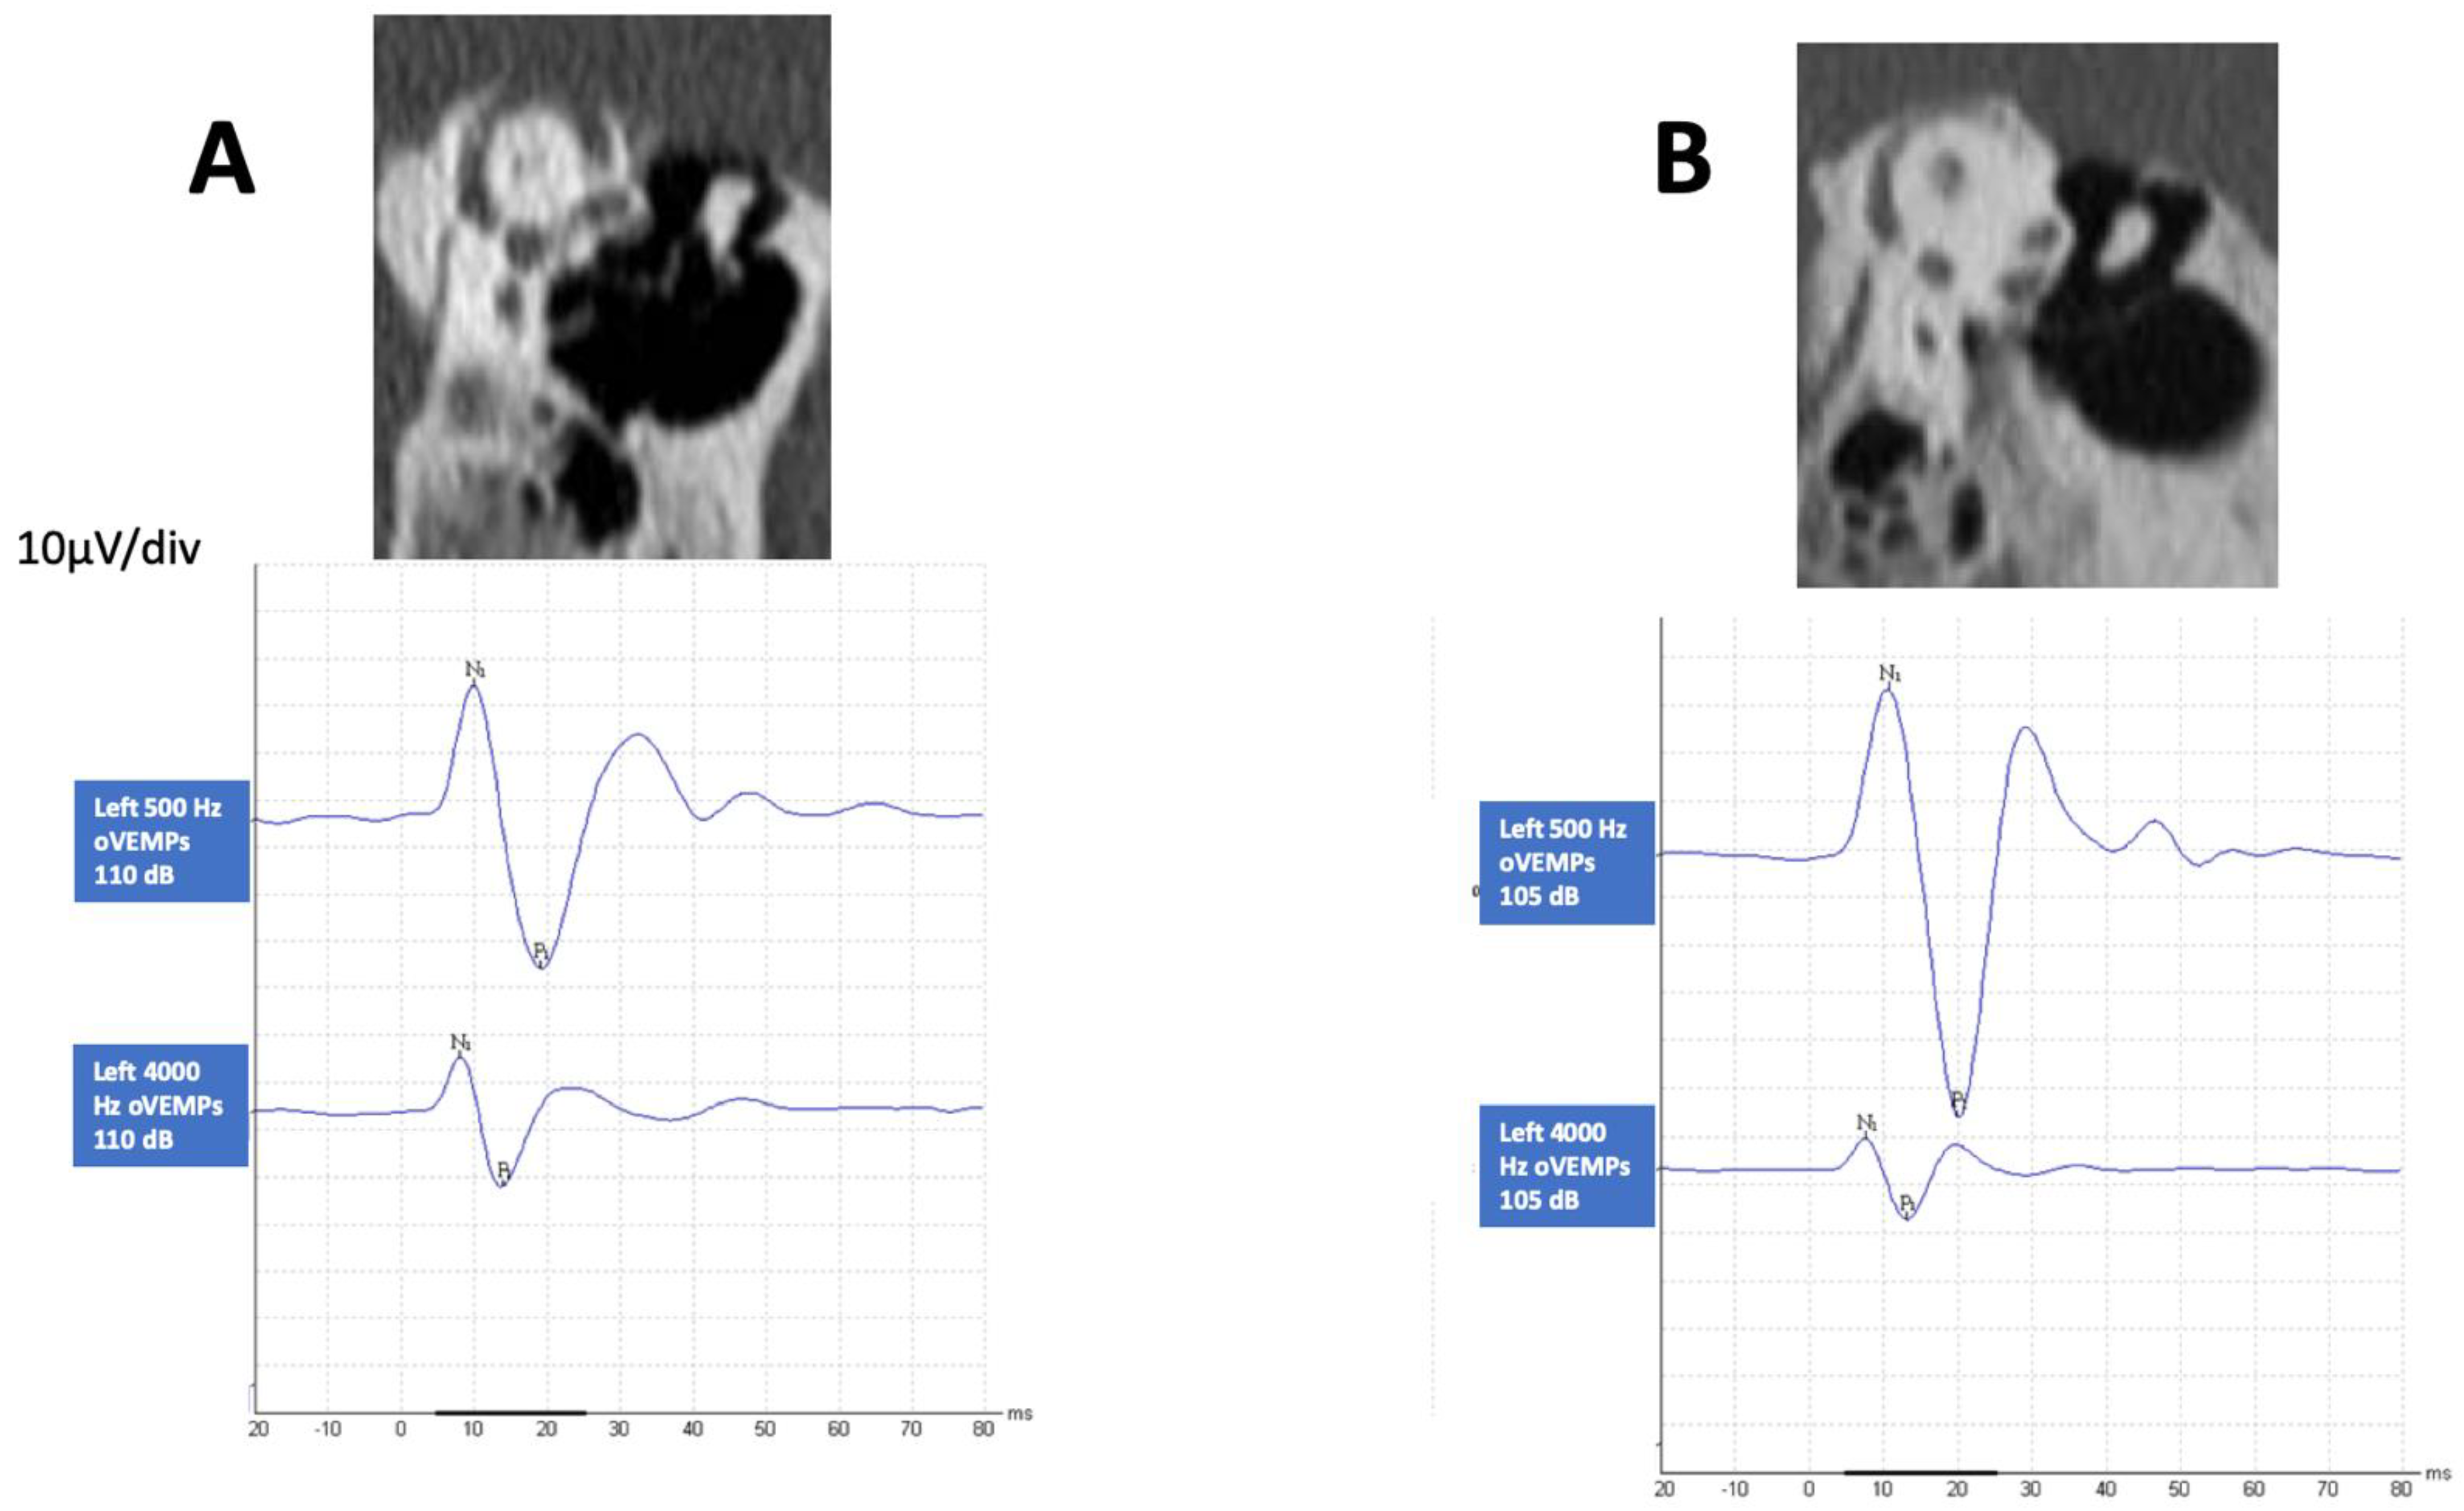

All patients had some degree of SCD in either or both ears according to radiology inclusion criteria. In 13 (43%) patients, one of the temporal bones was normal, and in the other, there was a near-dehiscent SSC (Superior Semicircular canal); in 9 (30%) patients, one side was normal, and in the other, there was a clear dehiscent SSC; in 5 (16.6%) patients, in both sides the SSC was dehiscent; in 2 (6.6%) patients, one side was dehiscent and the other near-dehiscent; in 1 (3.3%) patient, both sides were near-dehiscent. As shown in Table 1, bilateral SCD was found in 5 patients, and unilateral in 11 patients. Of the 60 temporal bones studied, no dehiscence was found in 22, near-dehiscence in 17 and a definite finding in 21. When a more precise classification was done, there were 14 patients in the SCD group and 16 in the SCD+ group; in 11, SCD was unilateral, and in 5, bilateral. In Figure 1, we present the CT scan image of two different cases showing both types of abnormality and the corresponding HFoVEMP.

Figure 1.

CT scan finding of two patients that shows a left definite dehiscence (A) and left near-dehiscence (B) with the corresponding oVEMP findings at 0.5 kHz and 4 kHz air-conducted sound stimulating each ear.